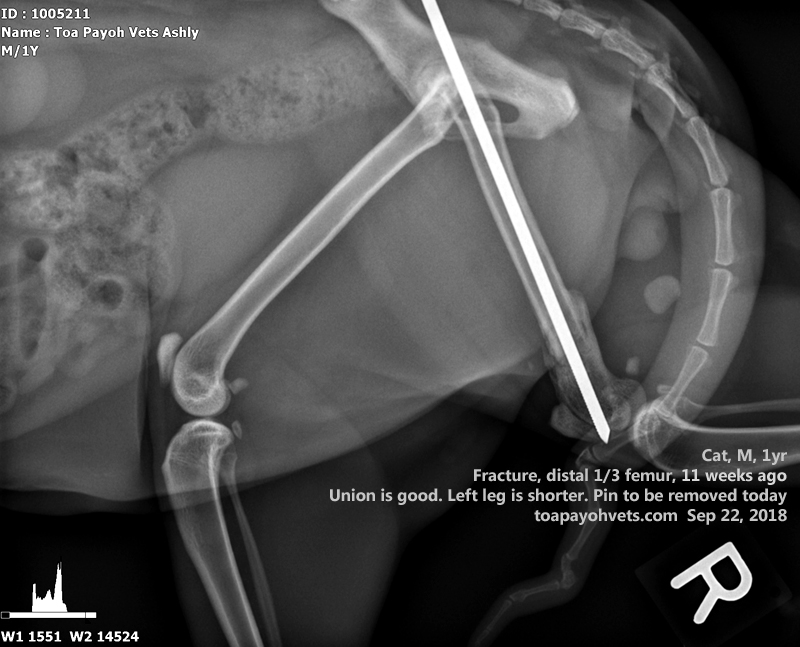

From 2010vets.blogspot.com

Veterinary, Photography and Travel Stories for vet students and pet Cat Hip Swollen Most cats with a hip dislocation will have severe hind limb lameness and may not be able to put any weight on the affected limb. It can affect one or all four of the cat’s legs. In this article, we look at some of the. Hip dysplasia is the medical term describing abnormal development of the hip joint. When a. Cat Hip Swollen.

Veterinary, Photography and Travel Stories for vet students and pet Cat Hip Swollen Hip dysplasia in cats is a genetically inherited malformation of the hip joint. Hip dysplasia refers to a malformation of the hip joint. Clinical signs of feline hip dysplasia include limping or other apparent difficulties in walking, avoidance of physical activity, expression of pain if the hip is touched, and persistent licking. In this article, we look at some of. Cat Hip Swollen.